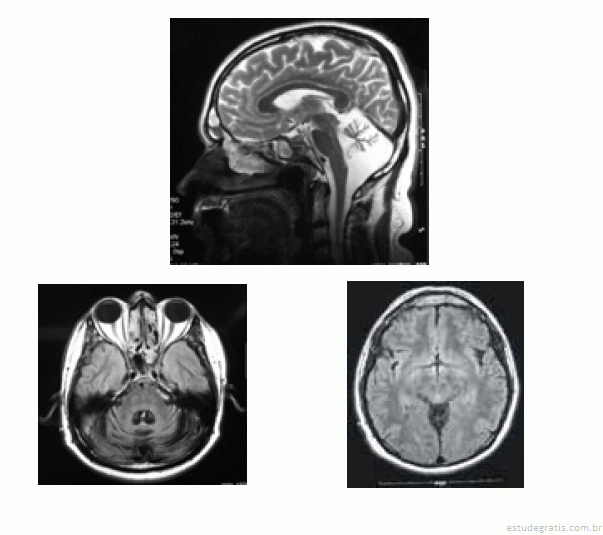

José, com 42 anos de idade, foi renovar sua carteira de motorista e, ainda na entrada do consultório, o médico observou uma marcha com base alargada e insegura. Durante a avaliação clínica, ao testar a coordenação, o médico verificou tremor de intenção à prova índex-nariz, dismetria e disdiacocinesia bilateral. Os pares cranianos, a força muscular e os reflexos — profundos e superficiais — eram normais. A fala de José era pausada, silabada. Ao ser questionado sobre o uso de álcool, negou-o e referiu que o problema do desequilíbrio vem piorando nos últimos dez anos, fato que provocou o acompanhamento médico e motivou a realização de uma ressonância nuclear magnética (RNM), cujas imagens são apresentadas abaixo.

Acerca desse quadro clínico, julgue os seguintes itens.

As imagens e o quadro clínico são incompatíveis com atrofia olivopontocerebelar.